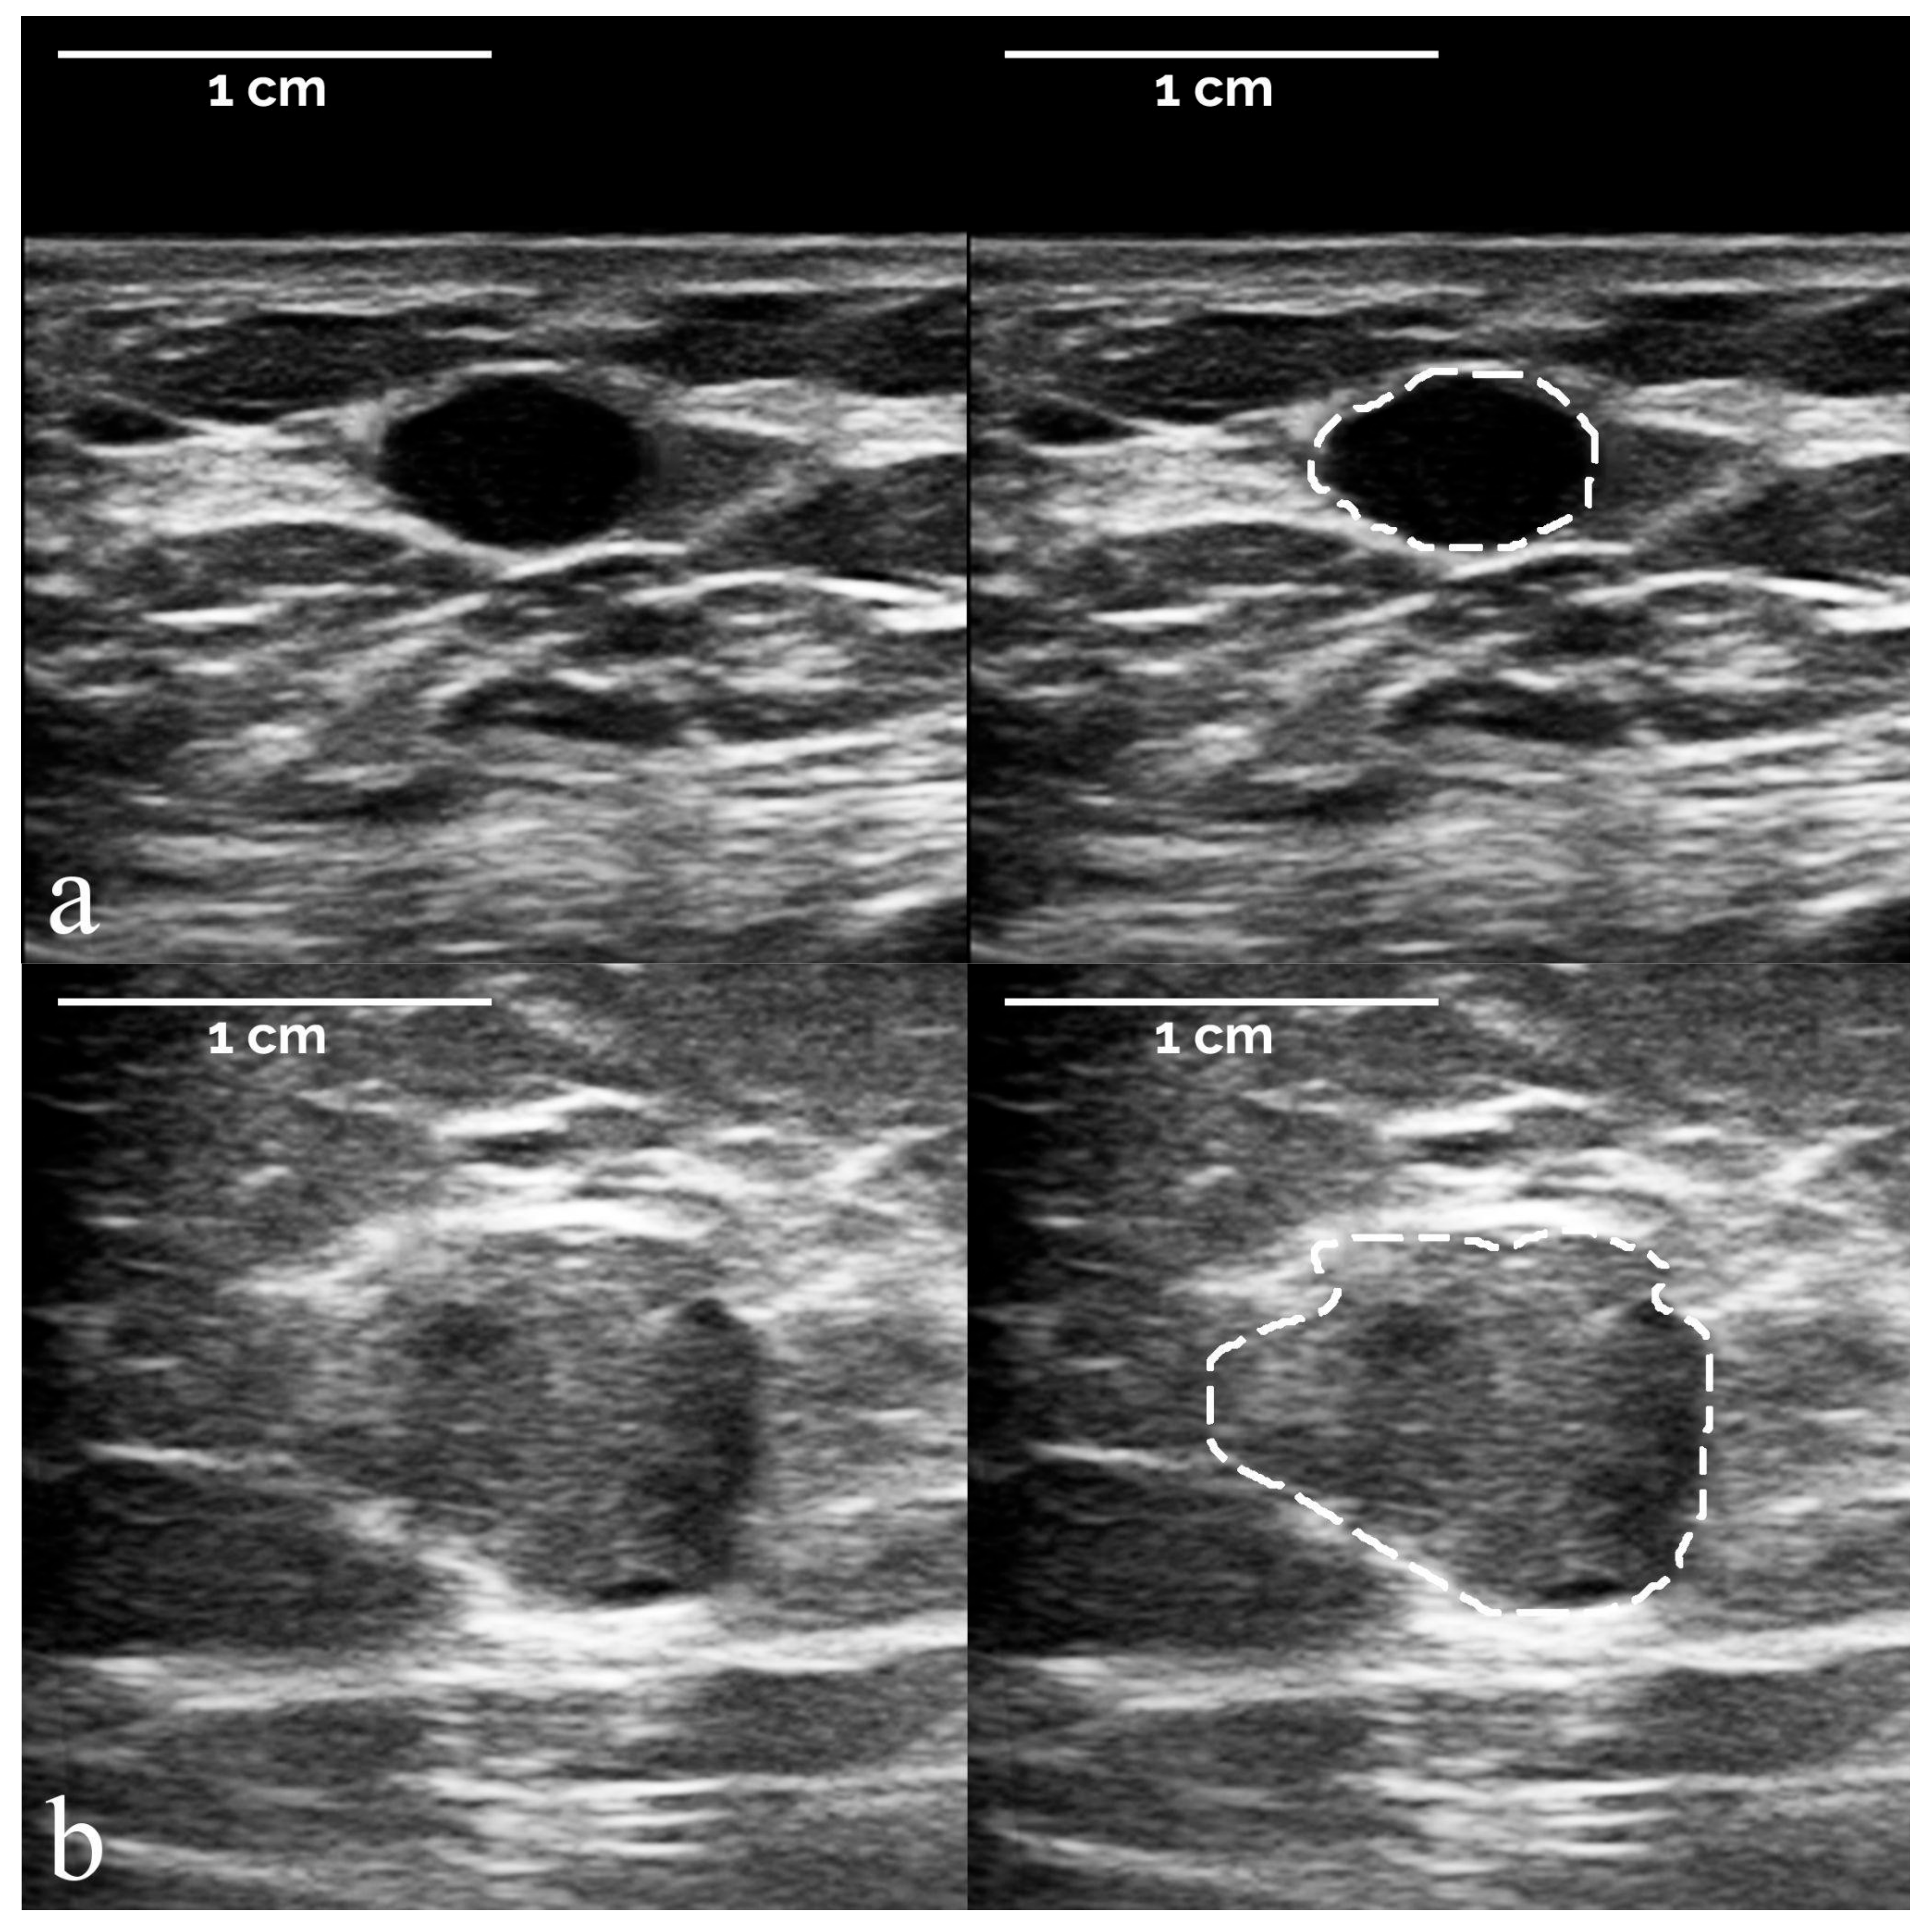

- The segmentation of suspicious masses on all 821 images was performed manually by a board-certified radiologist with 34 years of experience in breast imaging, using the TRACE4 segmentation tool. The same radiologist (at a time distance of 8 weeks) and a second board-certified radiologist with 7 years of experience independently segmented the masses on a random subsample of 50 images from the training dataset, fully blinded to histopathology and other segmentations.

3.1. Study Population and Image Sets

3.2. Radiomic-Based Machine Learning Modelling